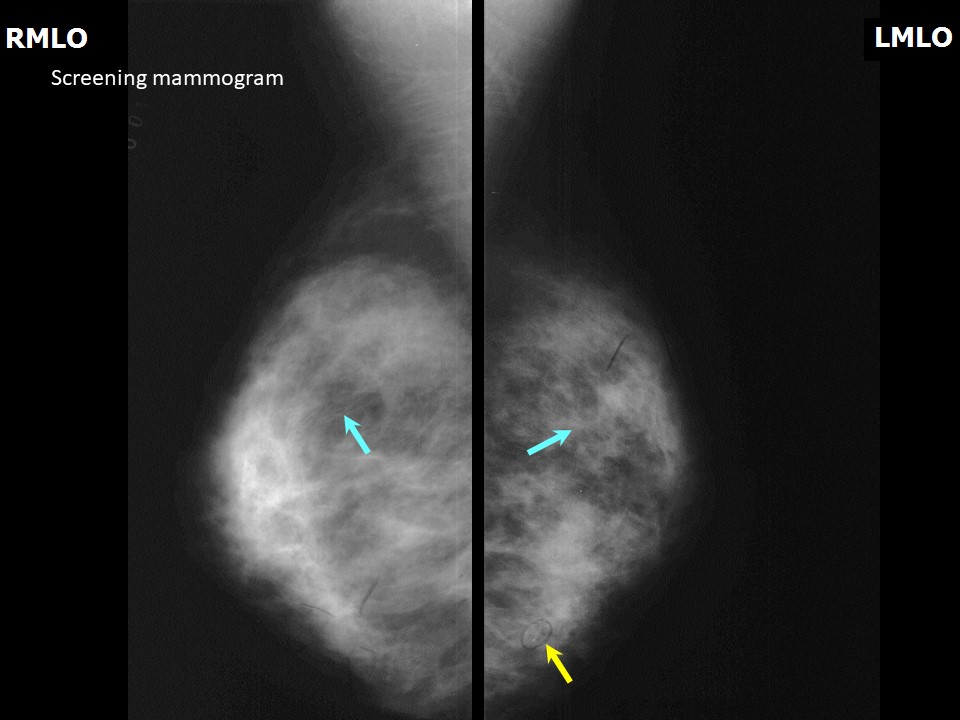

Феномен гипердиагностики в маммографии: примеры и иллюстрации

Раздел: Образы вокруг